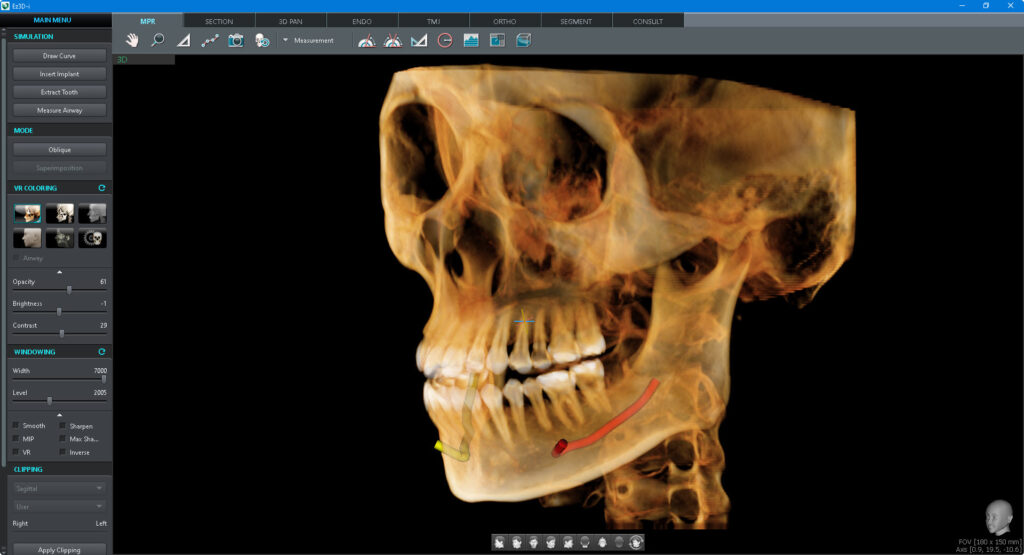

INTEGRACIÓN CAD/CAM

Nivel suficiente de detalle para el diseño de la guía quirúrgica

PLANTILLA ESPECIALMENTE DISEÑADA

Protección estable de modelo parcial a modelo completo.

Tomografía